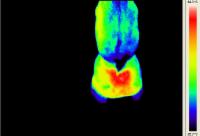

Temperaturwert = Farbwert | temperature value = colour value |

Rasmus - Pferd mit Arthrose - Horse with Osteoarthritis![]() Walzertraum - Pferd nach Sehnen-OP - Horse after tendon operation